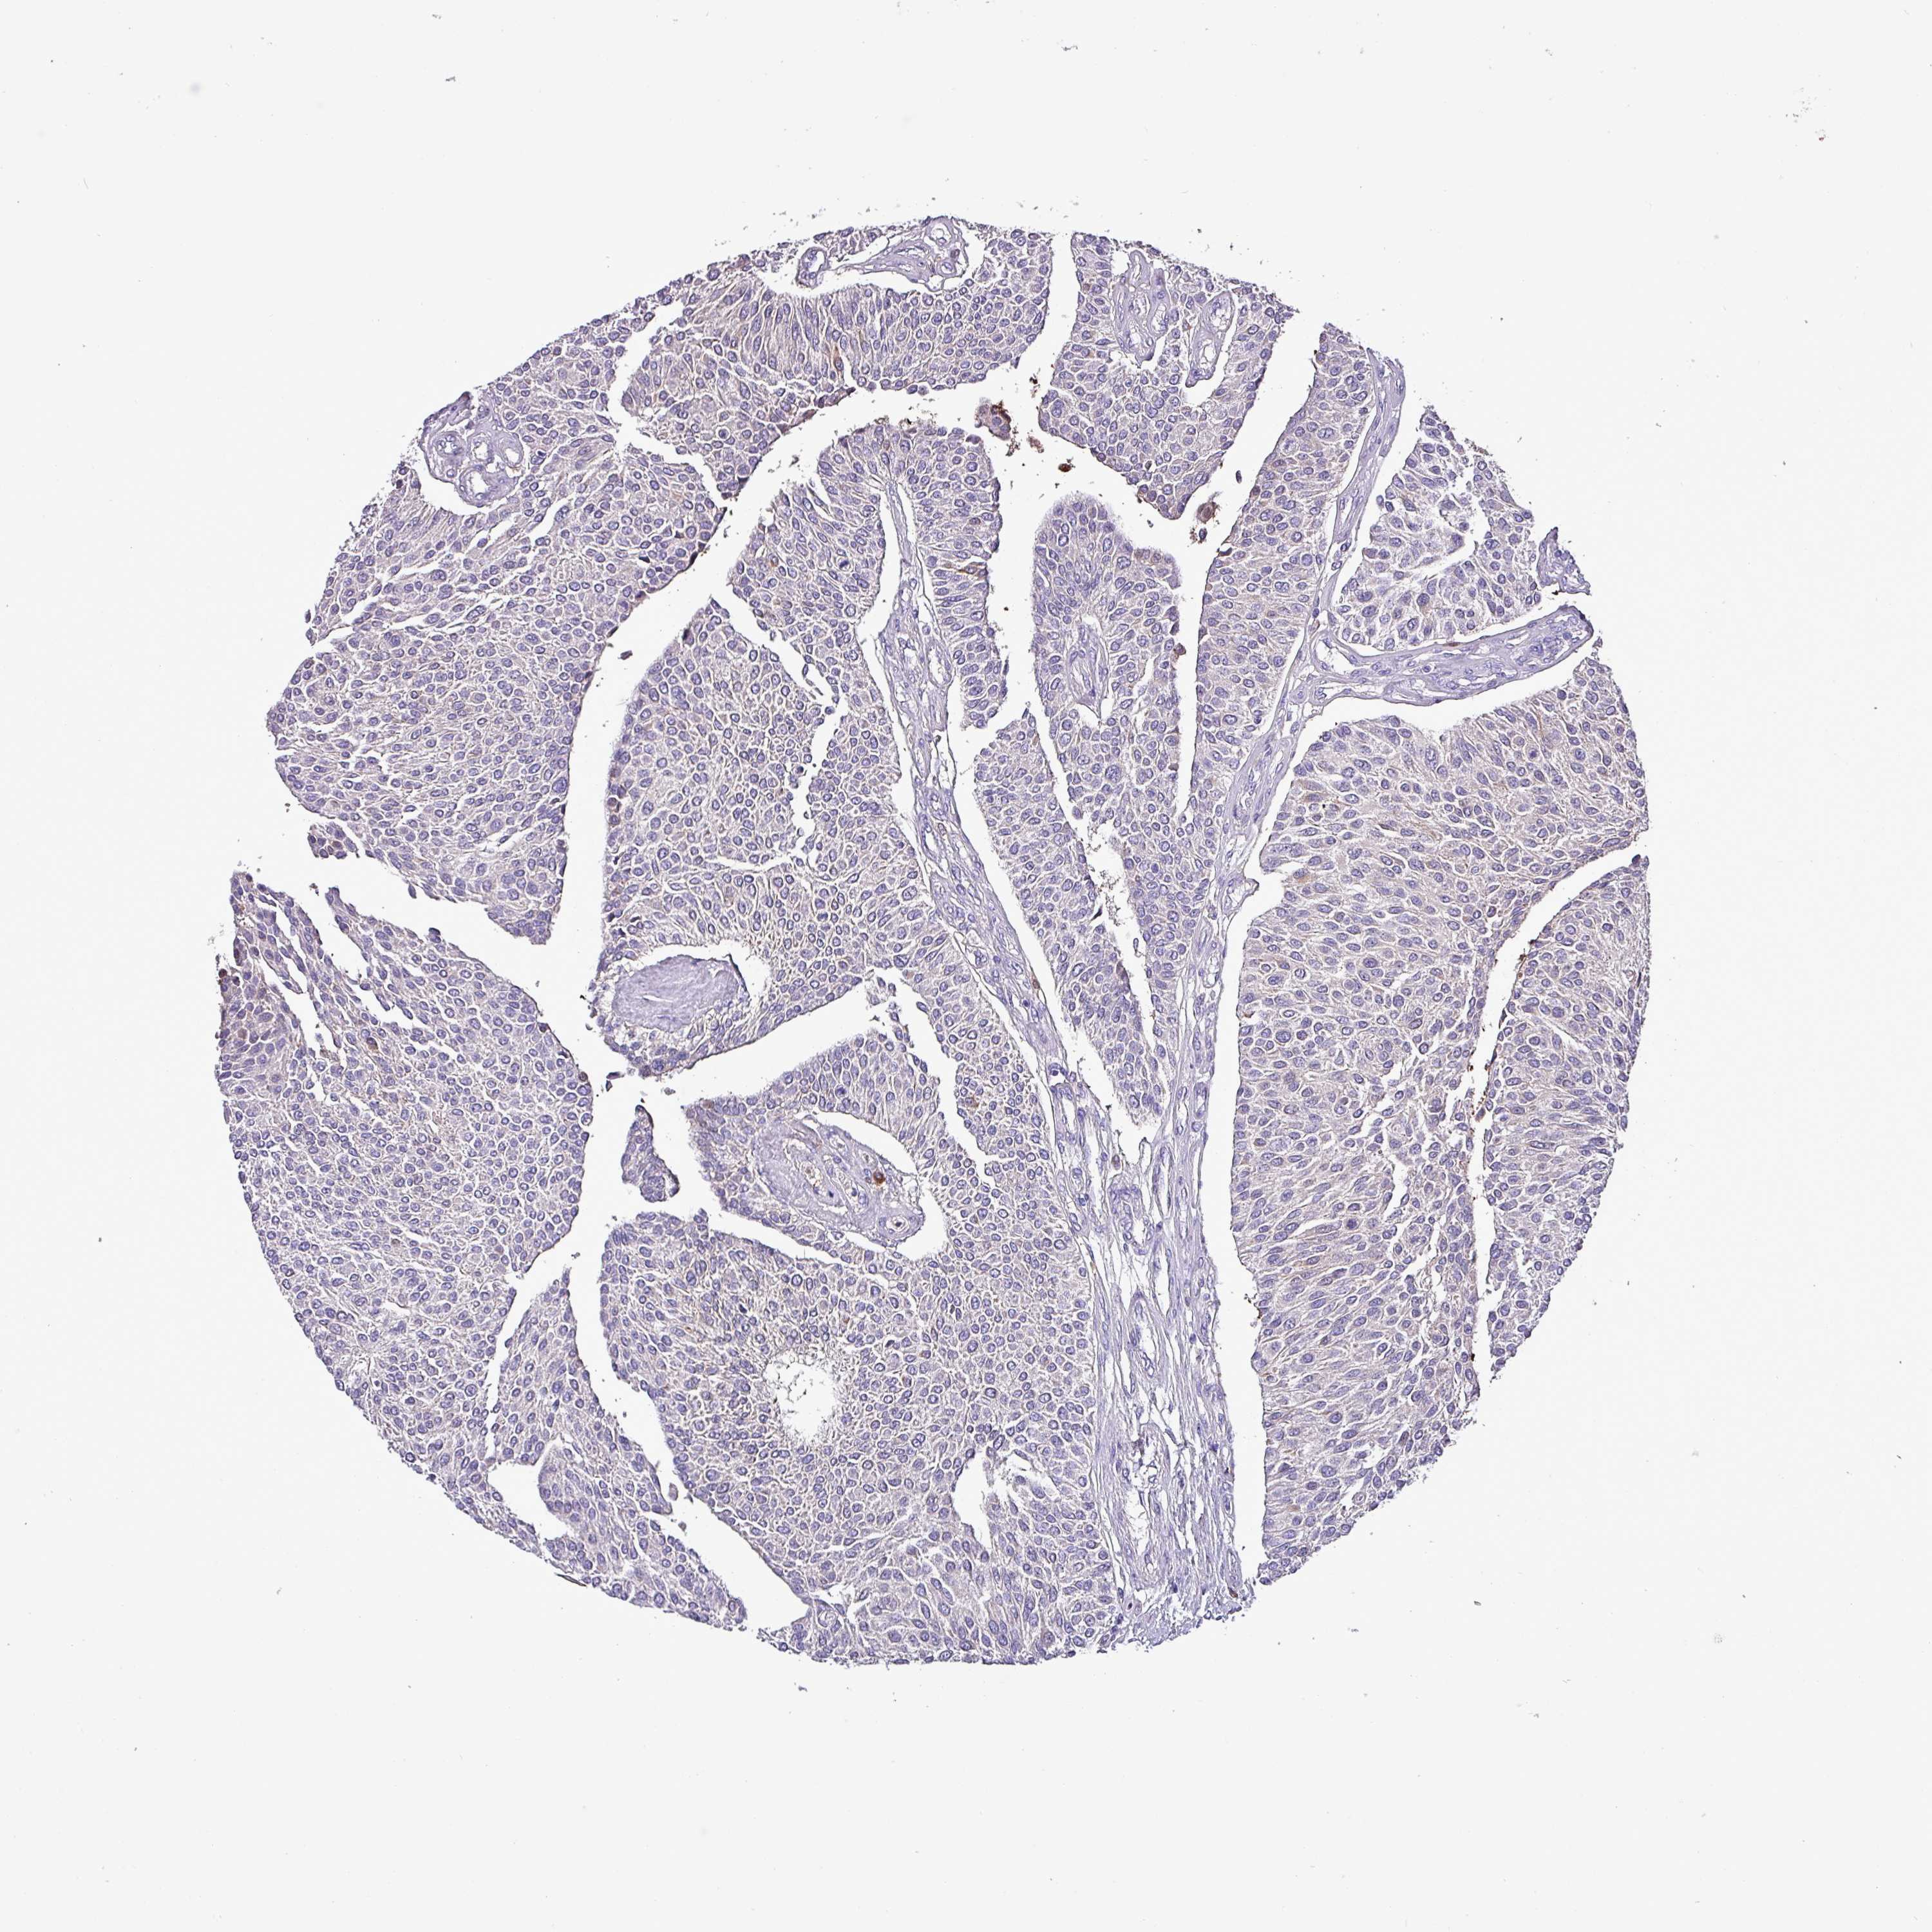

UROTHELIAL CANCER - Protein expressioni

A mouse-over function shows sample information and annotation data. Click on an image to view it in a full screen mode. Samples can be filtered based on level of antibody staining by selecting one or several of the following categories: high, medium, low and not detected. The assay and annotation is described here.

Note that samples used for immunohistochemistry by the Human Protein Atlas do not correspond to samples in the TCGA dataset.

Antibody stainingi

Antibody staining in the annotated cell types in the current human tissue is reported as not detected, low, medium, or high, based on conventional immunohistochemistry profiling in selected tissues. This score is based on the combination of the staining intensity and fraction of stained cells.

Each image is clickable and will lead to virtual microscopy that enables deeper exploration of all samples and also displays staining intensity scores, fraction scores and subcellular localization as well as patient and tissue information for each sample.

Antibody HPA047750

Staining

High

Medium

Low

Not detected

Intensity

Strong

Moderate

Weak

Negative

Quantity

>75%

75%-25%

<25%

None

Location

Nuclear

Cytoplasmic/membranous

Cytoplasmic/membranous,nuclear

Urothelial carcinoma, High grade

Urothelial carcinoma, NOS

Urothelial carcinoma, Low grade